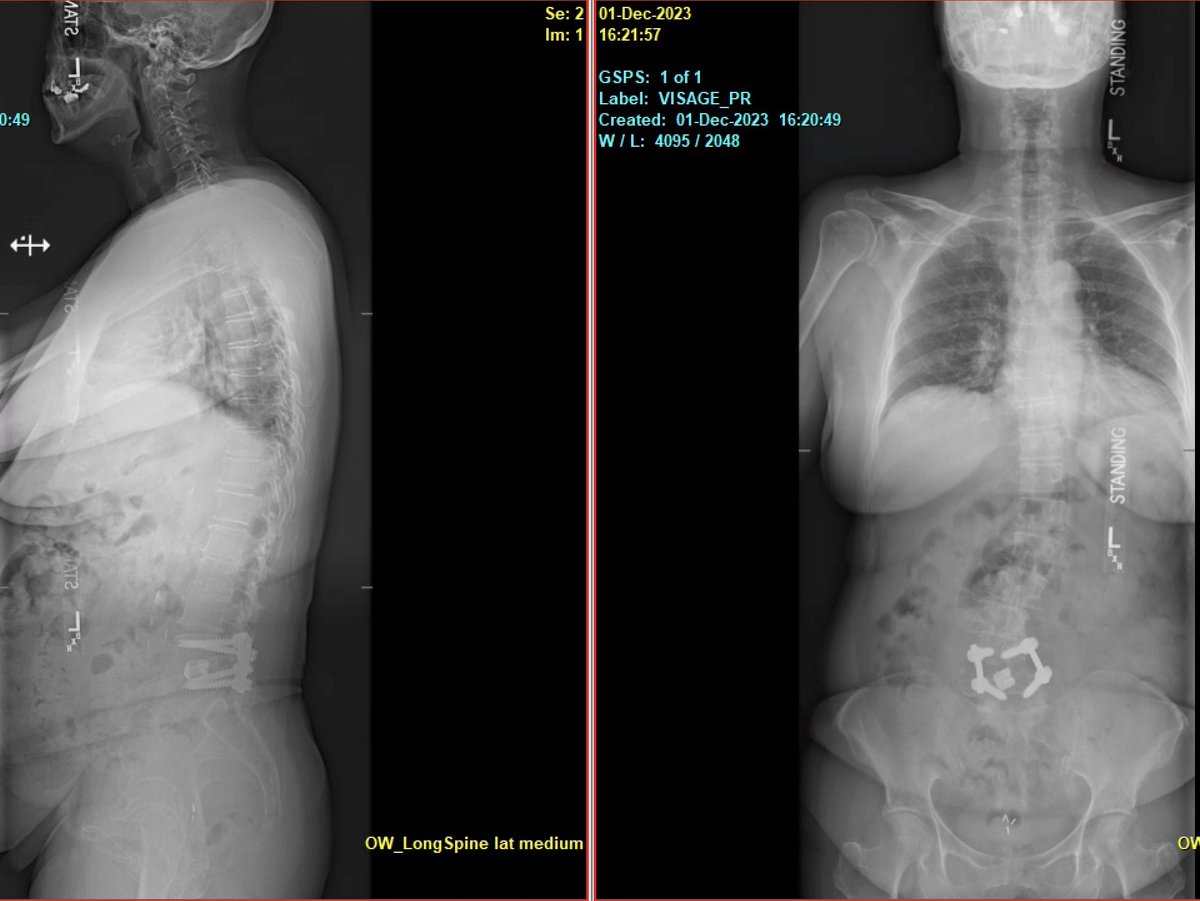

Pre-and post-op awake MIS fusion to correct this patient scoliosis. @mayoclinic our associate surgeon @RodNavarroMD work hand in hand to learn the latest approach, enabling technology and freehand. Accepting applications for 2024-2025. @DoctorQMd @oakinduroMD @wchrisfox

Very satisfying case not only because of the deformity correction we achieved but more importantly because of the impact this surgery had on the patient’s life. @MayoClinicNeuro patient specific 3D printing for planning. https://t.co/Nz6Yehvu7Y! For new appointments #scoliosis